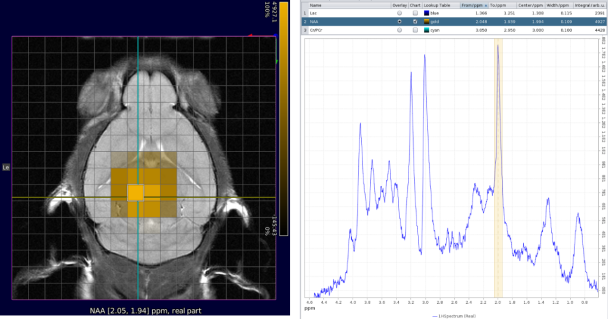

Extended spectroscopy capabilites

• AI-based baseline and phase correction

• Efficient visualization and processing of single-voxel spectroscopy and chemical shift imaging spectroscopic data (e.g., CSI) with Spectroscopy Card

• Metabolic map creation and anatomical reference image overlaying

• Spectral editing of J-coupled resonances such as lactate, γ-aminobutyric acid (GABA), glutamate, and glx (glutamate/glutamine) with MEGA-PRESS

CSI with NAA frequency mapped.

CSI with NAA frequency mapped. Image Credit: Bruker BioSpin Group